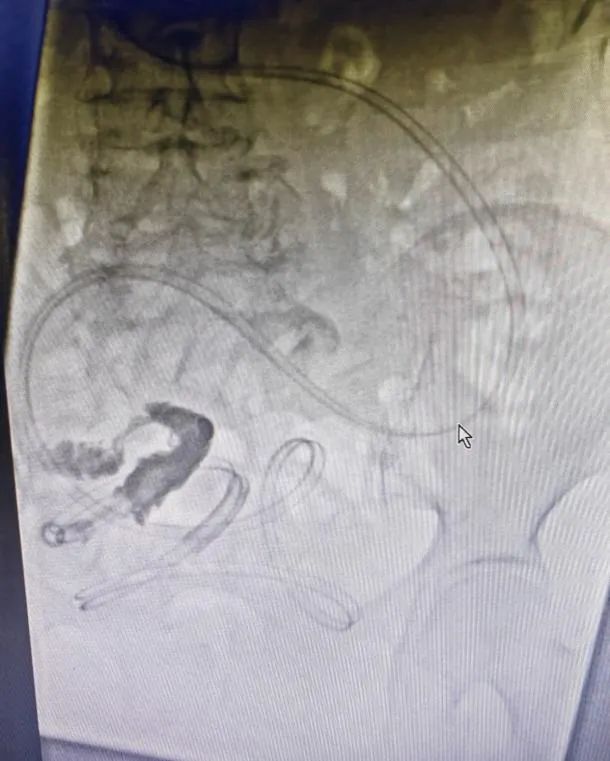

梗阻解除后复查造影片,见梗阻部位

术中情况

案例:患者,女,78岁,因“反复腹部胀痛伴肛门停止排气排便3年”入院,既往有阑尾切除术、输尿管结石切开取石术、输卵管结扎术、鼻咽癌放疗史,有多次肠梗阻住院保守治疗史,结合CT等检查,诊断为粘连性肠梗阻,入院后禁食、解痉、抗感染、补液等对症支持治疗后,症状未见明显缓解,且腹胀逐渐加重,在DSA下消化道造影及肠梗阻导管置入,术后第二天梗阻缓解,肛门排气排便,从而进食,待肠道功能完全恢复后择期行腹腔镜下肠粘连松解术,术后6天治愈出院。